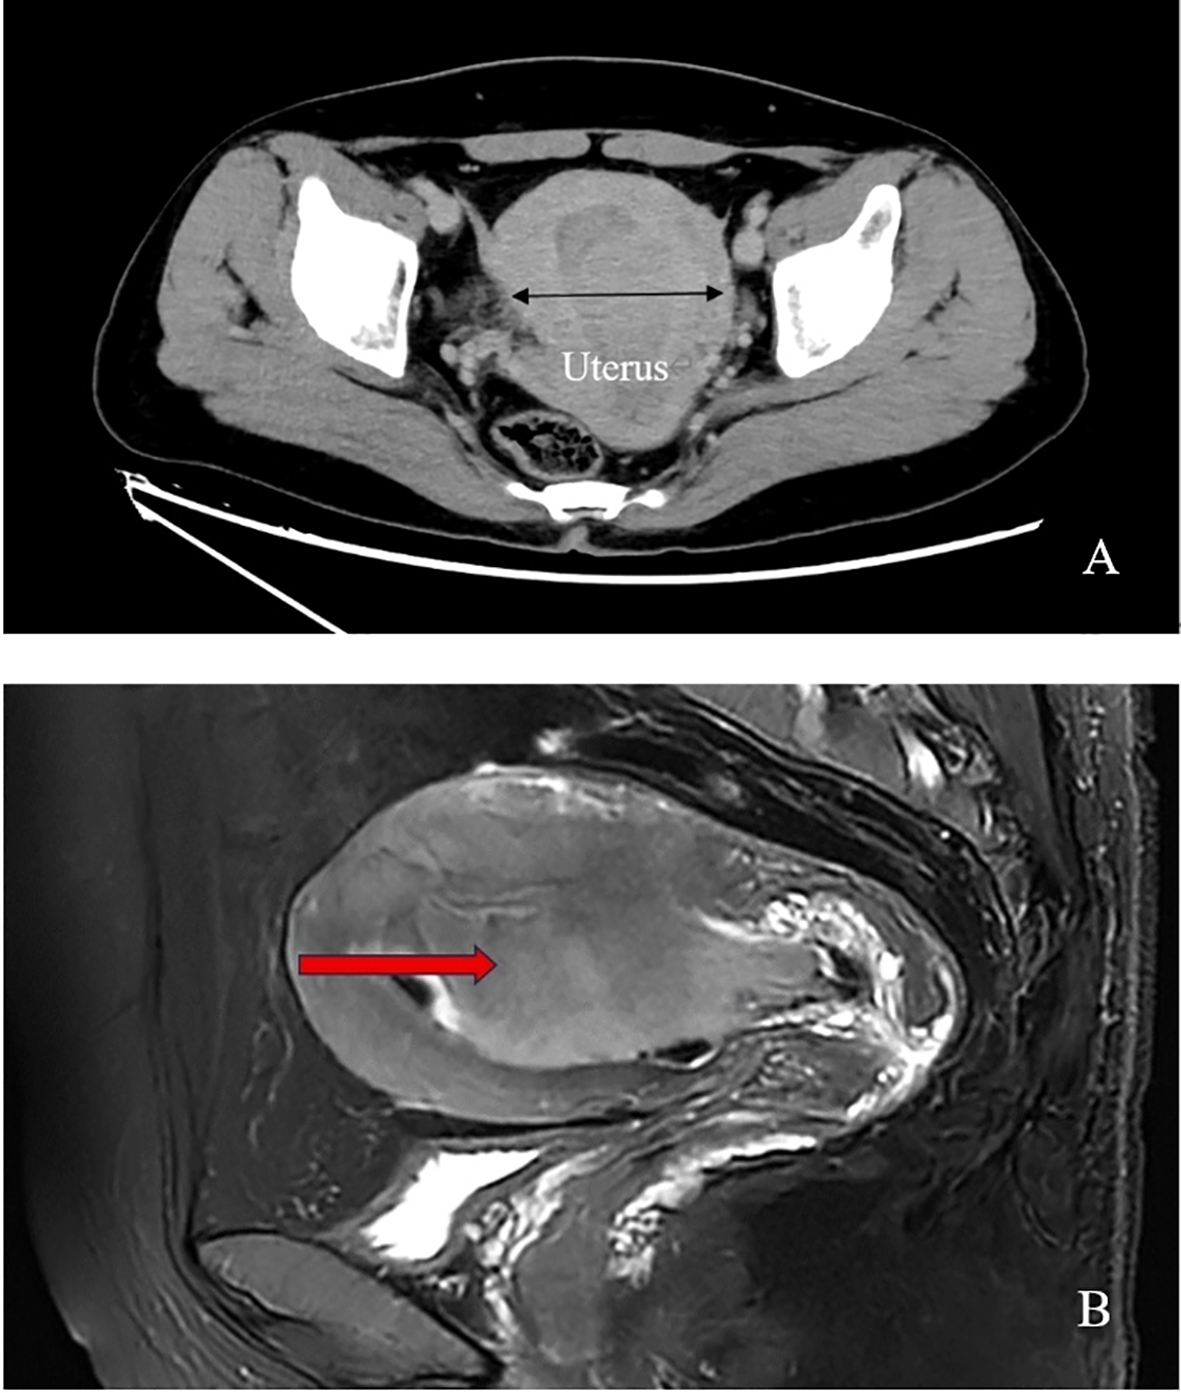

Enhanced computed tomography scan of the lower abdomen showed enlarged uterine volume, marked thickening of the left uterine wall, an oval-shaped mass protruding from the uterine cavity with a maximum cross-sectional dimension of approximately 36 × 71 mm, marked enhancement after contrast administration, normal bladder filling, no obvious enlarged pelvic lymph nodes, and no obvious pelvic effusion (Figure 1A). The examination mentioned above showed an enlarged uterine volume, marked thickening of the left uterine wall, and an elliptical mass protruding from the uterine cavity, suggesting a possible sarcoma. Pelvic magnetic resonance imaging with contrast showed an elliptical abnormal signal focus measuring approximately 42.7 × 71.5 mm in the uterine cavity, appearing as low signal on T1-weighted images and slightly higher signal on T2-weighted images, with restricted diffusion. The lesion had unclear boundaries with the left posterior uterine wall muscle layer and showed significant enhancement after contrast administration (Figure 1B). A scar shadow was seen on the anterior wall of the lower uterine segment; multiple Nabothian cysts were observed in the cervix; there was a small amount of blood in the uterine cavity; and no obvious enlarged lymph node or fluid accumulation was seen in the pelvis. No obvious abnormal enhancement foci were observed after contrast administration. Based on these findings, the possibility of a uterine endometrial stromal sarcoma was suspected. Concurrent pathological assessment showed small, round to short, spindle-shaped tumor cells with infiltrative growth in the endometrial layer and myometrium of the uterus. The cells were of uniform size and had a mild pleomorphism, with mitotic figures <5 per 10 high-power fields (HPF). Based on the immunohistochemical findings, the diagnosis was suspected to be a mesenchymal tumor of intermediate or low malignancy grade. Therefore, close follow-up was recommended. Immunohistochemistry results showed positive pan-cytokeratin and desmin. CD34, H-caldesmon, HMB45, MyoD1, myogenin, SF-1, and SALL4 were negative. Ki67 was 5%. Based on the pathological assessment, it was difficult to definitively categorize the tumor as benign or malignant; however, potential for malignant transformation was suggested. Considering the patient’s age, marital status, reproductive history, and risk of malignancy, and excluding contraindications for surgery, laparoscopic total hysterectomy, bilateral adnexal resection, and retroperitoneal lymph node biopsy were performed. During the procedure, the uterus was enlarged to the size of a 3-month gravid uterus; bilateral ovaries and fallopian tubes appeared normal. However, there were partial adhesions between the bilateral fallopian tubes, ovaries, uterine wall, and intestinal tract. During the procedure, the uterus was incised, and a protruding, hard mass measuring approximately 6×4 cm was observed within the uterine cavity (Figure 2A). The surgery was performed smoothly, and approximately 300 mL of blood was lost during the procedure. The patient recovered well after surgery. Postoperative pathological assessment of the resected uterus and bilateral adnexa showed small, round to short, spindle-shaped tumor cells intermingled with the smooth muscle of the uterine wall. The cells were uniform in size and had mild pleomorphism, with mitotic figures 2-3 per 10 HPF (Figure 2B). Immunohistochemistry indicated the following findings: the tumor cells were positive for pancytokeratin (Figure 2C), vimentin, desmin(Figure 2D), and calretinin and weakly positive for WT-1, D2-40, CK5/6, and ALK. HMB45, h-caldesmon, MyoD1, myogenin, INSM-1, CD56, CD34, ERG, cyclin D1, SF-1, and SALL4 were negative; Ki67 was 5%. Based on the previous curettage biopsy and postoperative immunohistochemical results, the patient was diagnosed with epithelioid STUMP. The tumor exhibited infiltrative growth at its periphery, indicating malignant potential. Therefore, a close follow-up was recommended. The resected specimen also showed endometrial hyperplasia, chronic cervicitis, Nabothian cysts, multiple follicular cysts in both ovaries, and paramesonephric duct cysts. However, as the final pathology did not indicate a malignant tumor, no adjuvant therapy, such as radiotherapy or chemotherapy, was administered. The patient was discharged smoothly on the 7th day post-surgery. The last follow - up after surgery showed that the patient had not recurred for 8 months. Timeline of the patient’s disease and treatment course was shown in Figure 3. CARE Checklist of information was summarized in the Supplementary Data Sheet 1.

Figure 1

(A) Pelvic enhanced computed tomography scan of the patient shows increased uterine size and a protruding oval-shaped mass in the uterine cavity; (B) Pelvic magnetic resonance imaging reveals an anteverted and bulky uterus with a large oval-shaped mass (arrow point) occupying the entire uterine cavity, resulting in blur endothelium.